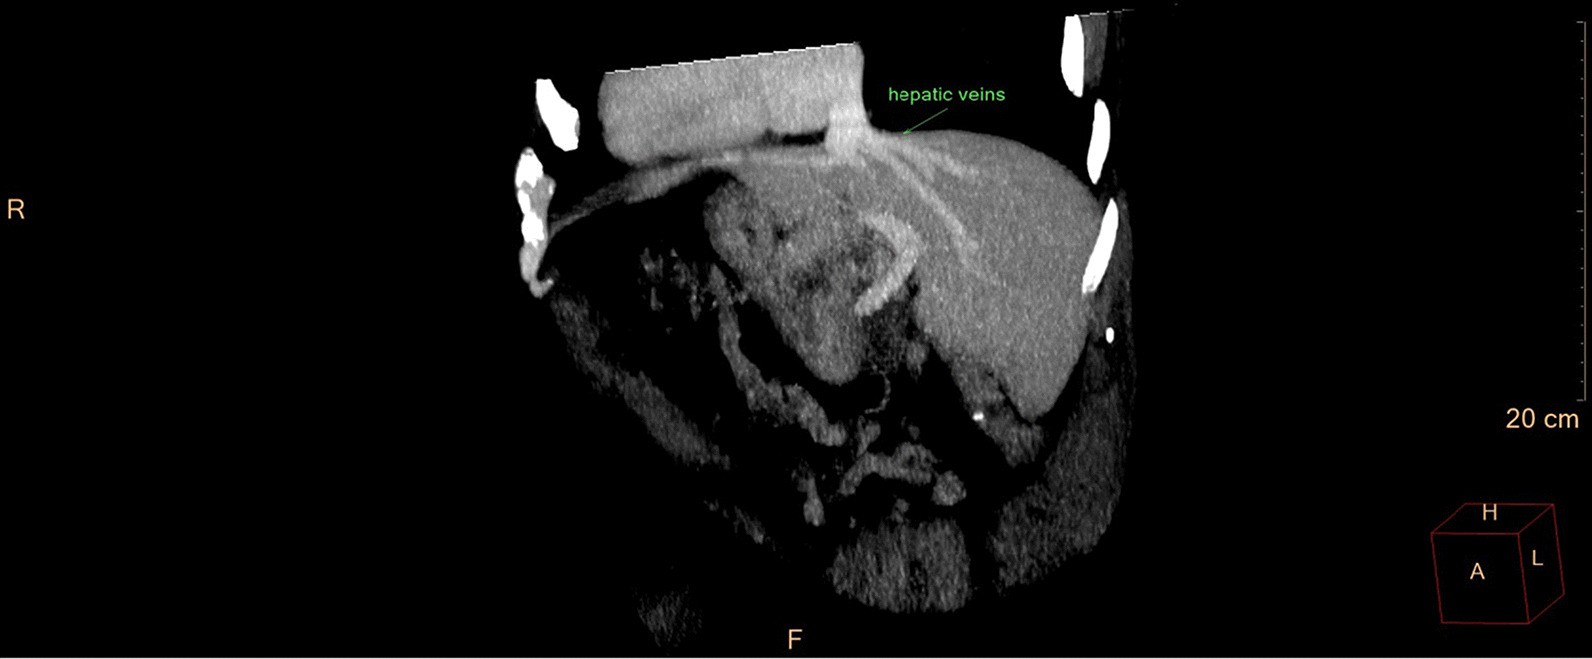

CT—maximum intensity projection—all hepatic veins drain directly into the atrium